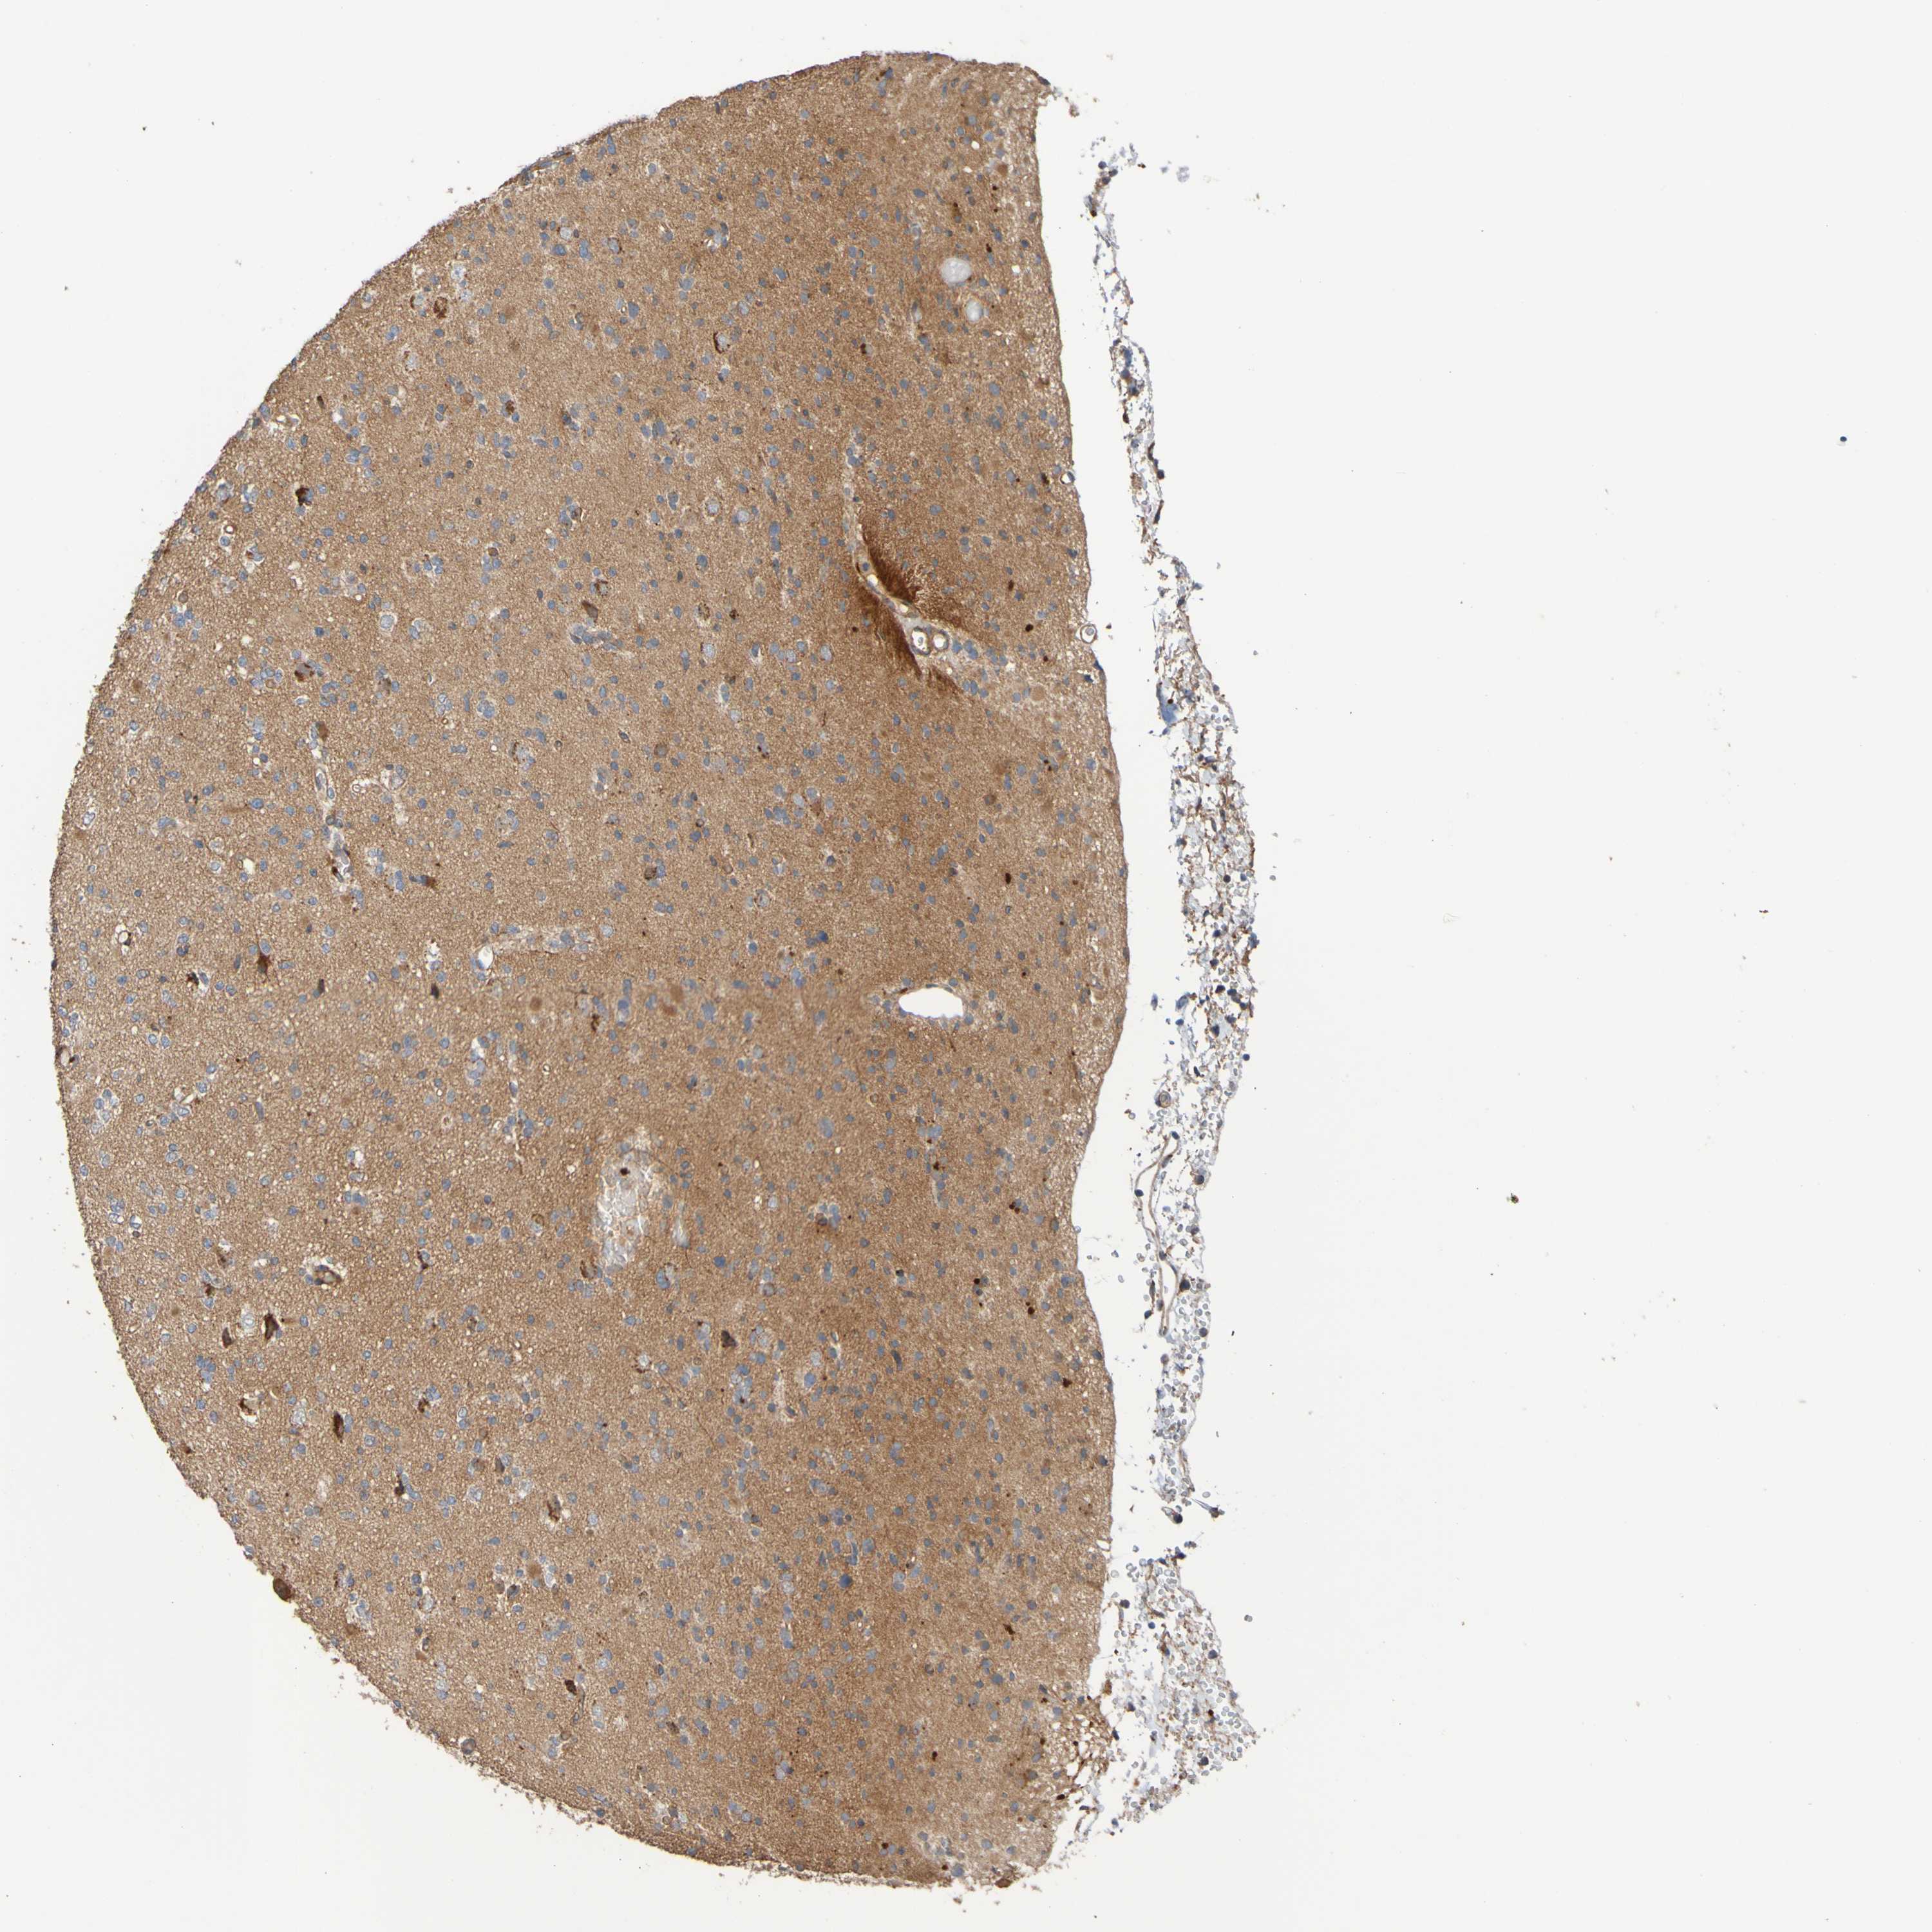

GLIOMA - Protein expressioni

A mouse-over function shows sample information and annotation data. Click on an image to view it in a full screen mode. Samples can be filtered based on level of antibody staining by selecting one or several of the following categories: high, medium, low and not detected. The assay and annotation is described here.

Note that samples used for immunohistochemistry by the Human Protein Atlas do not correspond to samples in the TCGA dataset.

Antibody stainingi

Antibody staining in the annotated cell types in the current human tissue is reported as not detected, low, medium, or high, based on conventional immunohistochemistry profiling in selected tissues. This score is based on the combination of the staining intensity and fraction of stained cells.

Each image is clickable and will lead to virtual microscopy that enables deeper exploration of all samples and also displays staining intensity scores, fraction scores and subcellular localization as well as patient and tissue information for each sample.

Antibody CAB010911

Staining

High

Medium

Low

Not detected

Intensity

Strong

Moderate

Weak

Negative

Quantity

>75%

75%-25%

<25%

None

Location

Nuclear

Cytoplasmic/membranous

Cytoplasmic/membranous,nuclear

Glioma, malignant, High grade

Glioma, malignant, Low grade